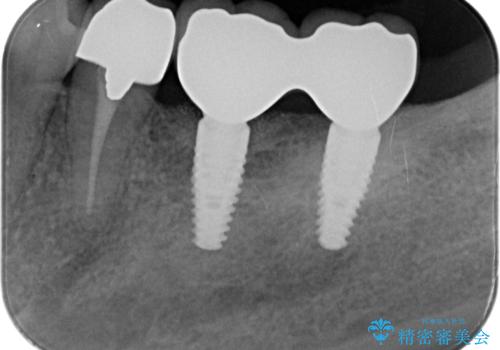

- 110万円(インプラント×2・チタンカスタムアバットメント×2・ジルコニアクラウン×3・仮歯×3 ・遊離歯肉移植術)費用は治療当時の料金となります

インプラント周囲のお掃除のしやすさを高め、長期的な予後を見込むために、遊離歯肉移植術を行っています。